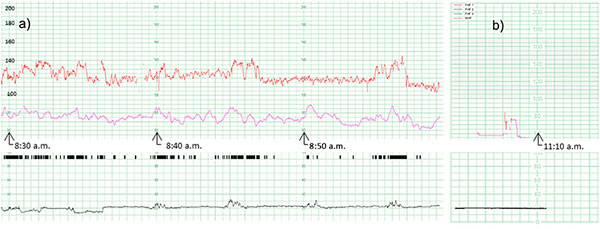

- КТГ фіксує частоту серцевих скорочень плода (ФСС) та тонус, а також наявність і частоту скорочень матки.

4. Основні параметри оцінки КТГ

- Базальна частота серця плода (110–160 ударів за хвилину в нормі).

- Варіабельність серцевого ритму (незначні коливання частоти).

- Наявність прискорень (ускорення серцебиття) — хороший знак.

- Відсутність чи наявність уповільнень серцебиття (децелерацій), які можуть свідчити про гіпоксію.